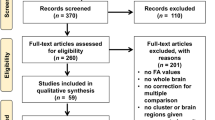

Data processing was performed with the Tensor Imaging and Fiber Tracking (TIFT) software package [23] which has been successfully applied to animal DTI group studies (e.g. [26, 27]). A schematic overview of the analysis cascade is provided in Fig. 1.